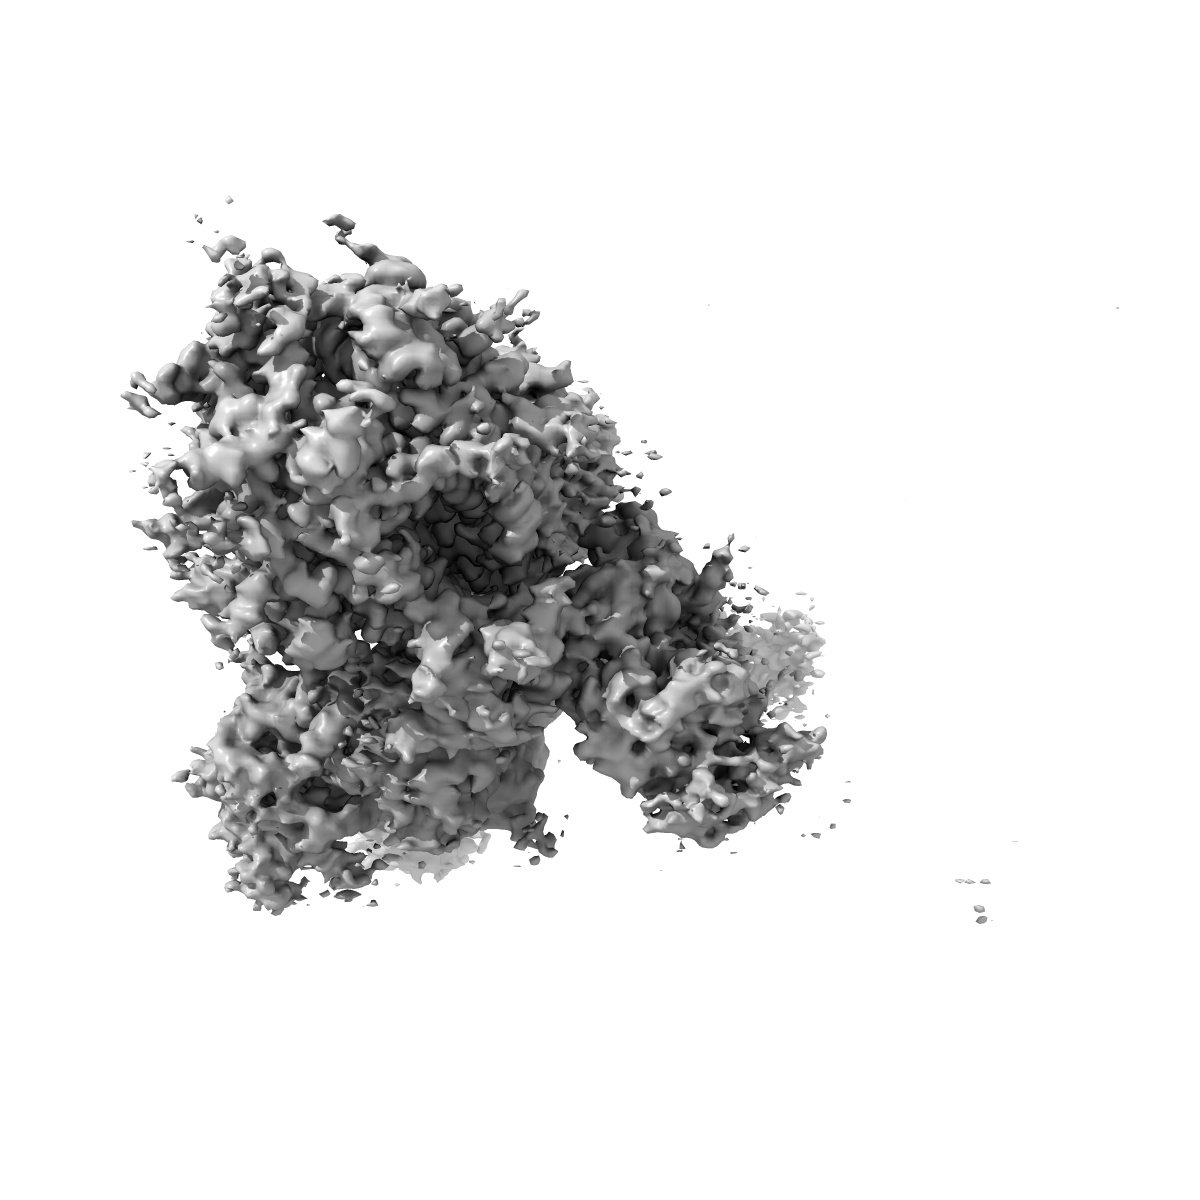

SARS-CoV 2 Spike Protein bound to LY-CoV555

Single-particle3.27 Å

Sample: SARS-CoV-2 spike protein bound to neutralizing antibody LY-CoV555

Fitted models: 7l3n